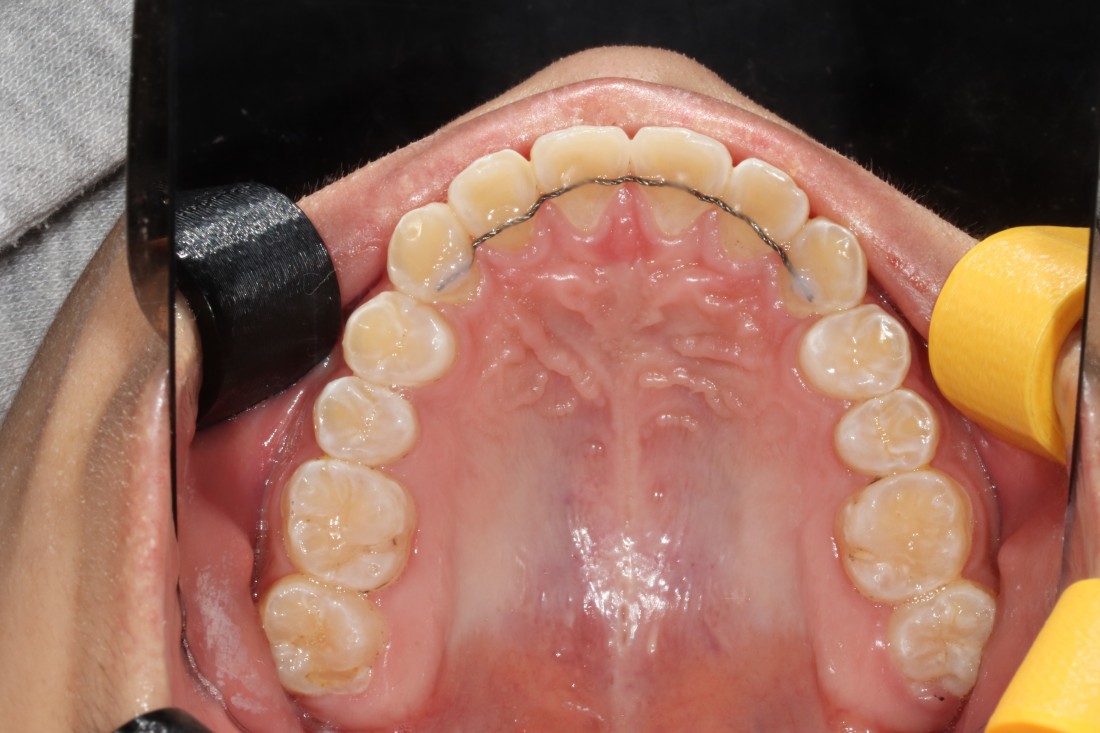

교정 전 정밀검사 비용,

발치비용,

교정장치 (클리피씨) 비용,

월 진료비용,

유지장치 비용 등

교정진료에 필요한

모든 비용을 포함한 금액으로

추가비용 결제 없는 치과